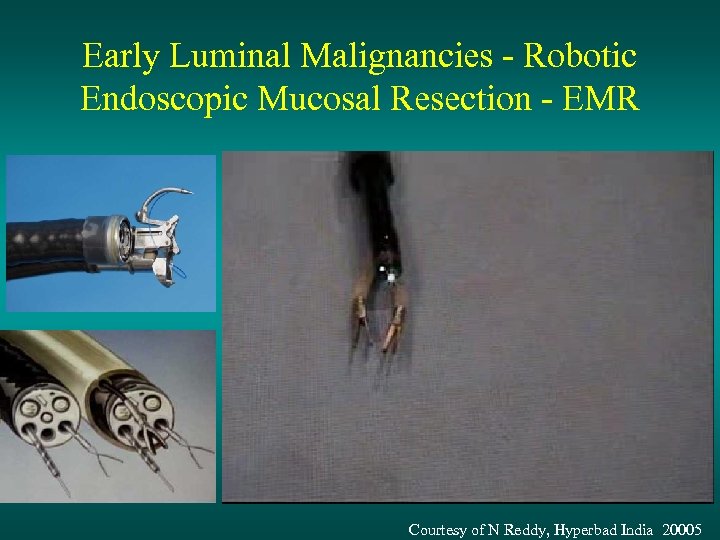

Early Luminal Malignancies - Robotic Endoscopic Mucosal Resection - EMR Courtesy of N Reddy, Hyperbad India 20005

Early Luminal Malignancies - Robotic Endoscopic Mucosal Resection - EMR Courtesy of N Reddy, Hyperbad India 20005